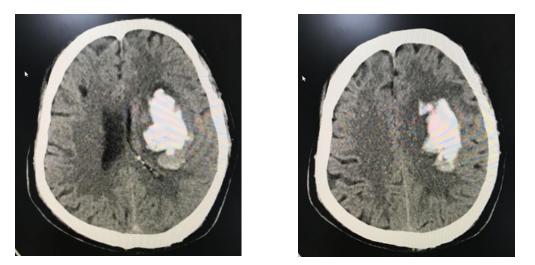

患者为老年男性,在凌晨4点钟做家政服务时突发剧烈头痛,倒身在地,逐步出现意识障碍,早上被人发现后送至苏州高新区人民医院,急查头颅CT提示左基底节脑出血,出血量达65ml,左侧侧脑室明显受压。

患者入院后,该院神经外科高山主任立即组织全科及麻醉科大讨论,商讨治疗方案。该患者身体比较瘦弱,出血对丘脑、内囊等重要结构造成破坏,对生命造成威胁,应立即手术清除血肿。传统开颅手术清除血肿对患者的创伤太大,可能对传导束进一步损伤,不利于术后恢复。相比较内镜下清除血肿,创伤小,视野好,经额血肿长轴入路便于彻底清除血肿并有效避免重要结构损伤。最终决定实行神经内镜下脑出血微创清除术。手术十分顺利,历时1小时左右,头皮切口隐秘设计在额纹中间,骨窗直径3cm,术中实现完全清除血肿,出血极少;术后,患者意识恢复清醒,肢体功恢复良好。